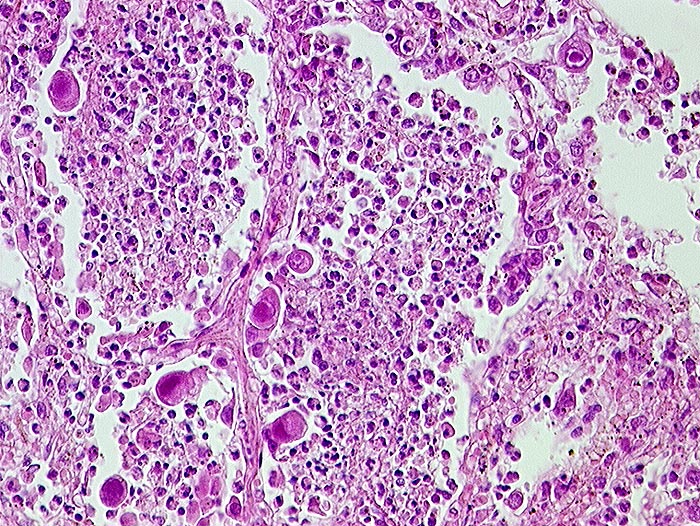

PathoPic – image database / PathoPic ID 218 - CMV (Zytomegalie) Pneumonie und Bronchopneumonie

CMV (Zytomegalie) Pneumonie und Bronchopneumonie

Virale Kerneinschlüsse mit Halo in Pneumozyten (sogenannte Eulenaugenzellen). Intraalveoläre Granulozyten bei zusätzlicher bakterieller Pneumonie.

HIV positiv seit 5 Jahren. Nachweis von zytomegalen Zellen im Hirn, in der Lunge, im Gastrointestinaltrakt, den Nieren und der Nebenniere. Zusätzlich bakterielle Pneumonie.

Histologie